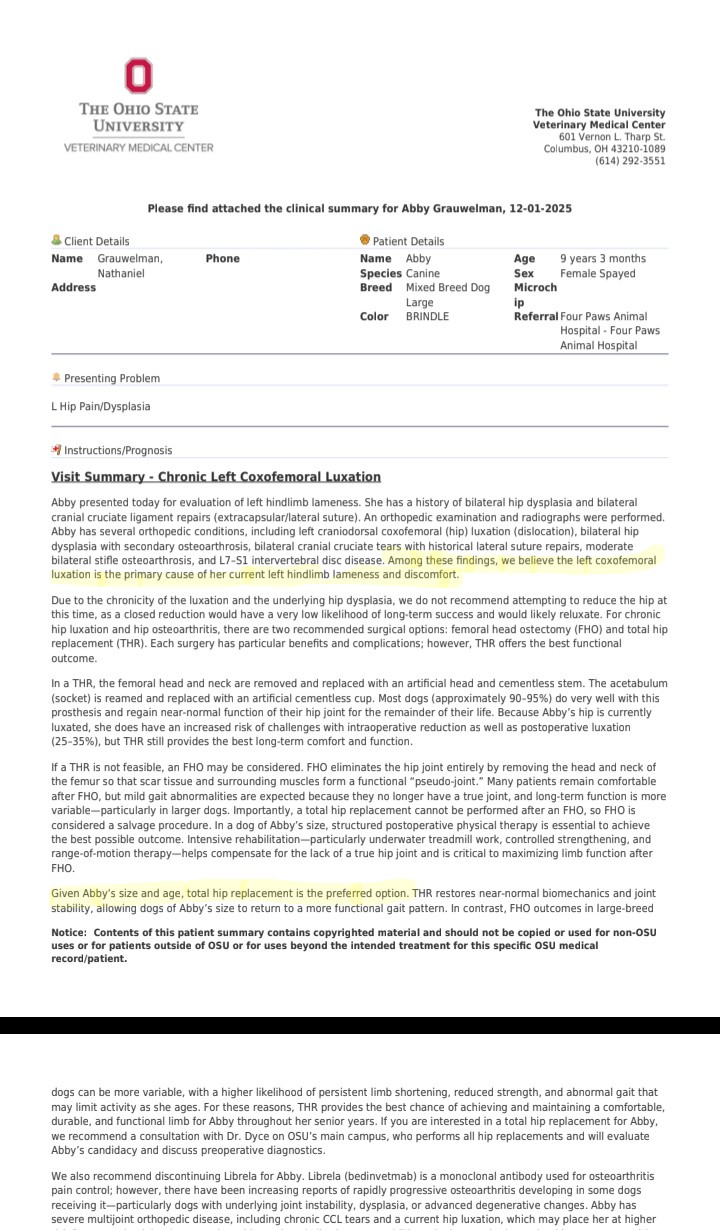

Because her current, maxed-out medication cocktail is still not enough to control this relentless pain, the specialists at OSU Veterinary College have determined that this luxation cannot be fixed by any other means than definitive surgery.

After Visit Summary from OSU

Our options are either an FHO (where they cut off the head of the femur and allow scar tissue to become a floating joint) or the preferred, yet costly, Total Hip Replacement (THR). The FHO isn't reccomend for dogs over 70lbs. Even when Abby loses more weight, she'll never be that light.